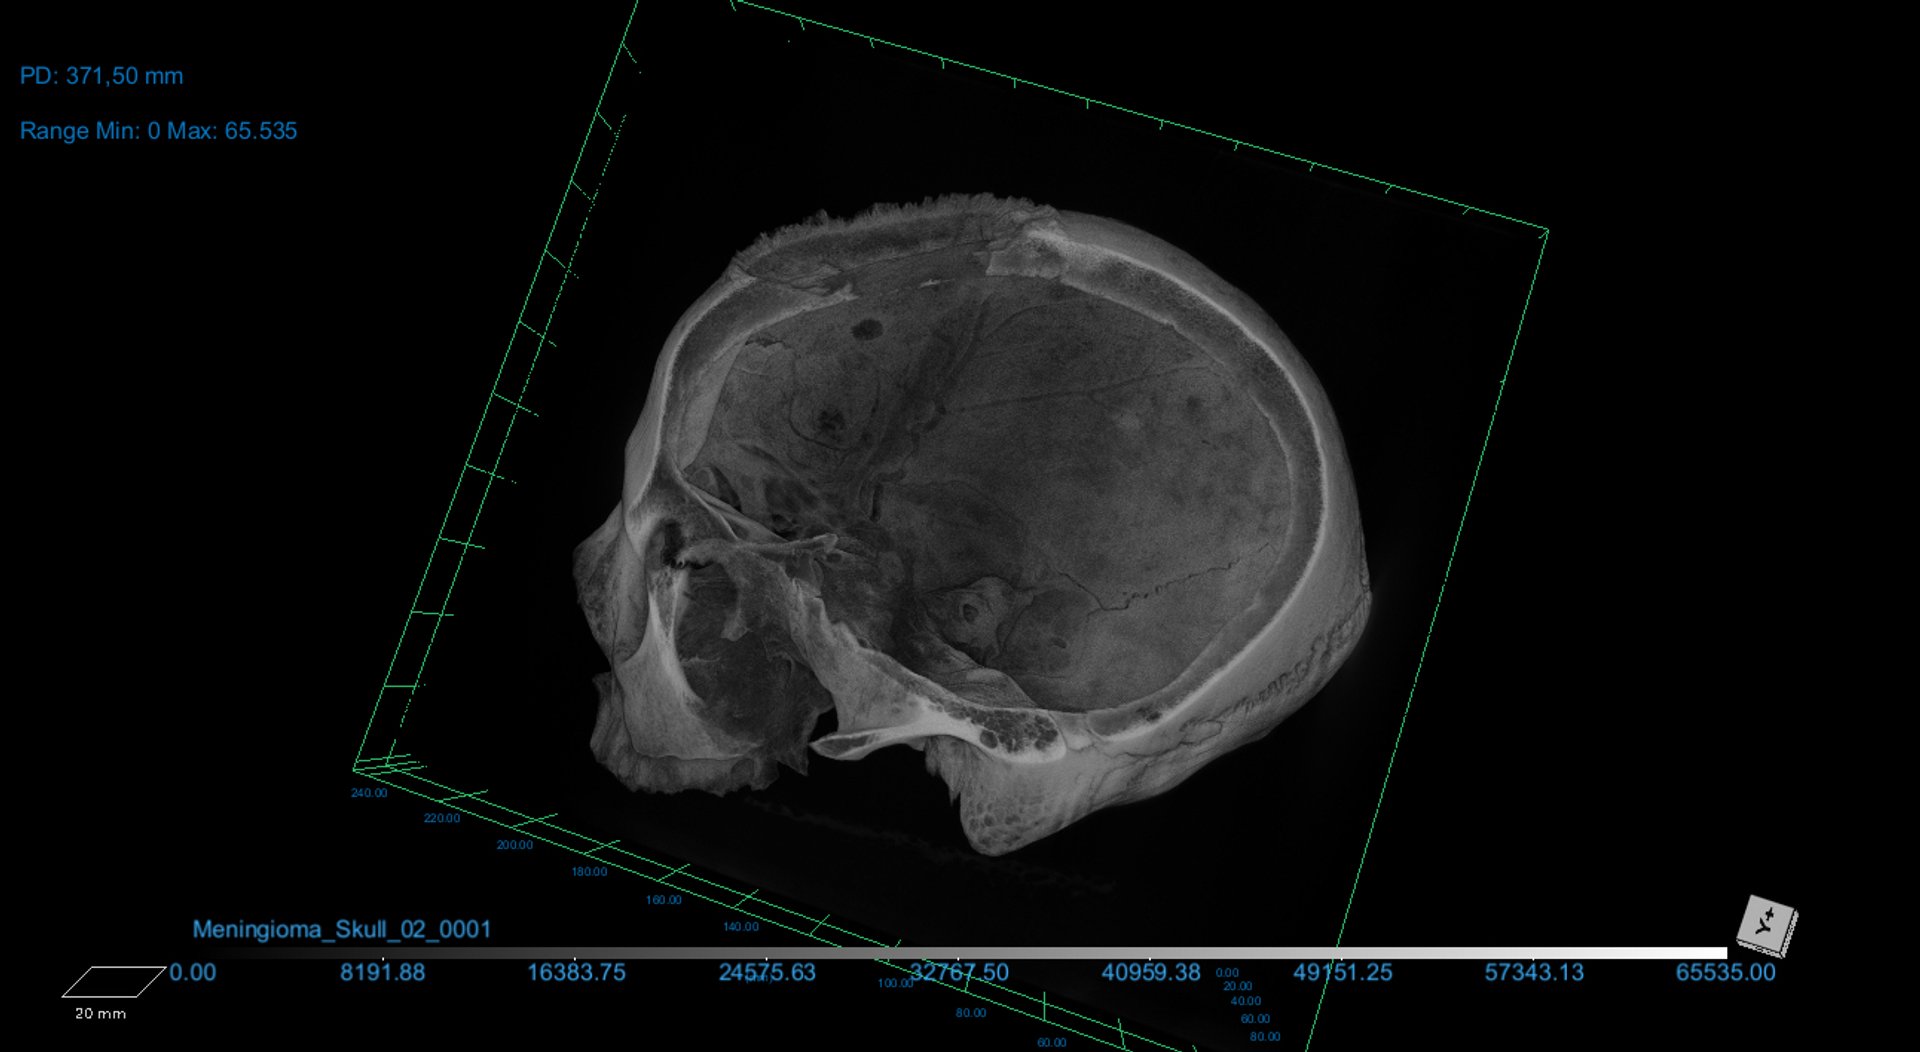

Camarós and his colleagues made the discovery while examining a skull that belonged to a man who died at around age 30 to 35, and lived sometime between 2687 and 2345 BC—ancient Egypt’s pyramid age. Using micro-CT scanning and microscopic bone surface analysis, they investigated a large lesion (an area of damaged tissue) and around 30 small and round metastasised lesions spread across the skull. It was around two of these small lesions that they spotted the tiny cut marks.

Cutmarks found on the skull, probably made with a sharp object

Tondini, Isidro, Camarós, 2024